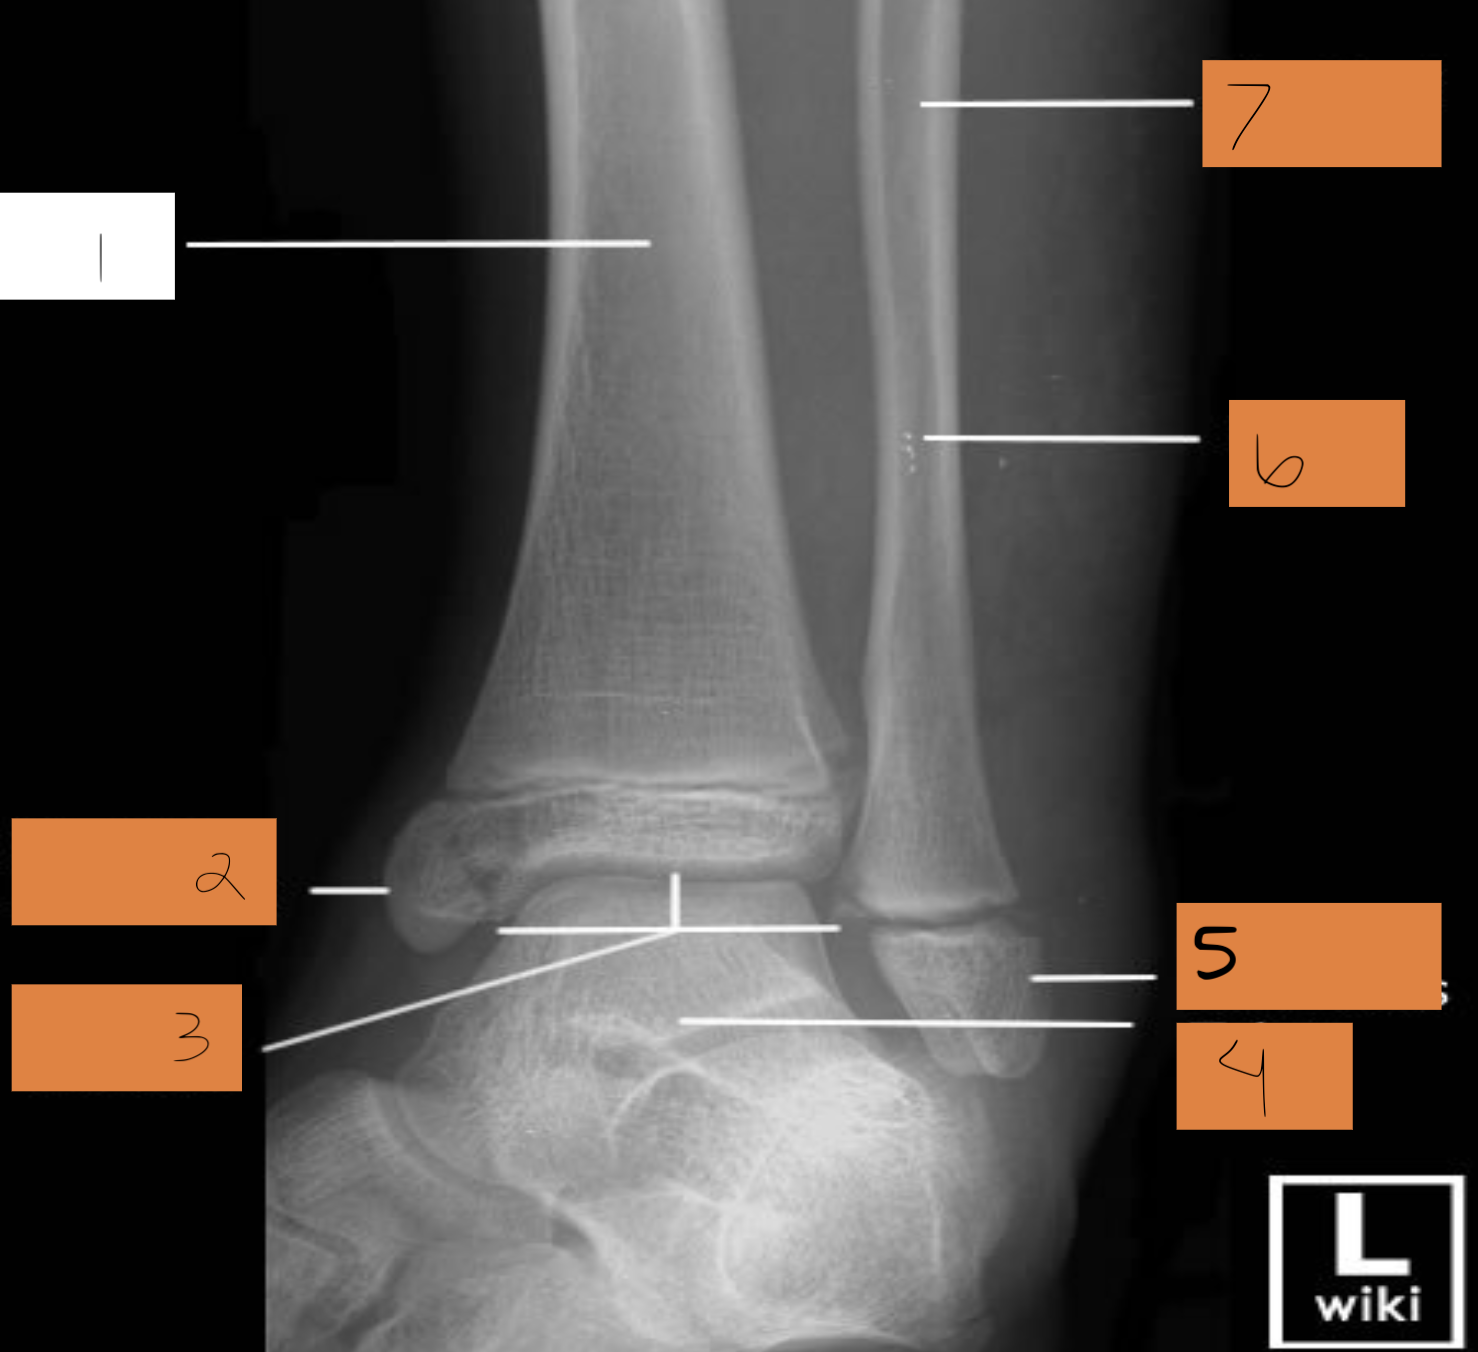

1

tibia

2

medial malleoulus

3

ankle mortise

4

talus

5

lateral malleolus

6

fibula

7

shaft of fibula